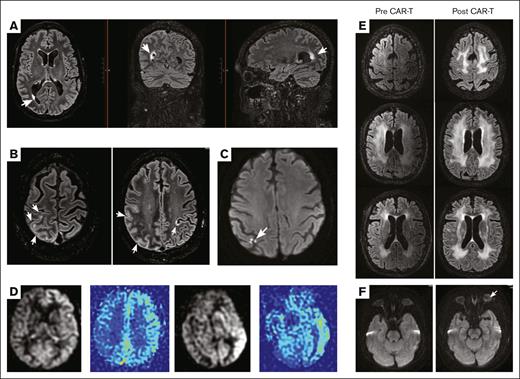

In contrast, MRI neuroimaging obtained in 7 patients with persistent neurological deficits demonstrated a high rate of acute imaging changes. The MRIs were performed at a median of 4 days after head CT. Of 7 patients with pretreatment and posttreatment MRI scans, 6 (86%) were found to have changes on MRI neuroimaging; 1 patient with grade 2 ICANS underwent a series follow-up brain MRI for MCL with CNS involvement after ICANS resolution. The patient with grade 3 ICANS shown in Figure 2E had follow-up imaging, which showed persistent white matter T2 hyperintensities 6 months after treatment. Otherwise, additional MRIs after ICANS resolution were not routinely performed if patients were neurologically stable at follow-up. Brain MRI changes during clinical ICANS include alterations across a range of MRI sequences, including diffusion weighted imaging (DWI), T1, T2 fluid attenuated inversion recovery (T2 FLAIR), gradient echo, and arterial spin label (ASL) sequences (Figure 2). One patient who had symptoms of perseveration and decreased speech output, left-right confusion, and left ankle clonus had marked T2 FLAIR hyperintensities in an area of right occipital cortex tissue adjacent to cerebrospinal fluid (CSF) and cortical fullness with additional abnormal T2 hyperintense signal along the right parietal-occipital cortical surface (Figure 2A-B). These imaging findings were asymmetric, affecting right more than left cerebral cortices. Another patient, who had expressive aphasia, decreased attention, and loss of orientation without other focal findings had a brain MRI revealing DWI abnormality that was punctate and in a nonvascular distribution (Figure 2C). In 2 other patients who presented with fluctuating mental status and aphasia, ASL sequences on MRI revealed asymmetric hyperemia in the left cerebral hemisphere (Figure 2D). In contrast, these patients did not have acute changes on T2 and DWI sequences. In 1 patient who had preexisting diffuse white matter lesions and underlying leukoencephalopathy of unknown etiology, the existing imaging abnormalities on T2 FLAIR significantly worsened during acute severe ICANS (Figure 2E). Additionally, he presented clinically with visual obscuration and additional evidence of bilateral optic nerve swelling on funduscopic examination, and supportive DWI hyperintensities were seen in optic nerves on neuroimaging (Figure 2F).

Brain MRI patterns after brexu-cel–associated ICANS. (A) MRI T2 FLAIR sequence showing focal hyperintensity at the right occipital horn. White arrow indicates the area of hyperintensity, visualized across axial (left), coronal (middle), and sagittal (right) cuts. The T2 hyperintense lesion is periventricular and located at the CSF and brain parenchymal border. (B) Additional MRI T2 FLAIR changes seen from patient examined in panel A. There is abnormal T2 hyperintensity and cortical fullness of right hemispheric parietal-occipital gyri. There is 1 area of notable T2 hyperintensity also on the contralateral side seen in the axial image to the right. As arrows indicate, these lesions contour along the meningeal surface of the brain. (C) MRI DWI sequence showing abnormal signal hyperintensity in the posterior right hemisphere. The multipunctate lesion has an atypical appearance at the juxtaposition of 3 cortical gyri and does not follow a specific vascular territory. (D) MRI ASL sequence from 2 patients with ICANS grade 3. Color maps further highlight the asymmetric hyperemia seen in the left hemisphere of both patients. (E) MRI T2 FLAIR sequence from a patient with preexisting white matter disease who then experienced grade 3 ICANS. The extension of white matter T2 hyperintensity increases between baseline before treatment (left column) and after treatment during ICANS (right column). Column images are axial views and arranged from rostral to caudal. (F) MRI DWI sequence from the same patient as in panel E, who experienced acute visual changes during grade 3 ICANS and found to have bilateral optic disk edema. White arrow indicates subtle increase in optic nerve DWI signal, left greater than right, that is seen in the postinfusion axial sequence (right) compared with baseline scan (left).

In contrast, we identified multiple discrete patterns of acute brain MRI changes across several distinct MRI sequences, which we hypothesize may represent the diverse spectrum of pathophysiology underlying ICANS. For example, Figure 2A-B shows abnormalities at the meningeal and cortical surface, as well as in a periventricular location between CSF and brain tissue. These imaging findings at “brain-border” tissues may suggest treatment-related immune interactions occurring at the systemic circulation and CNS interface. Although DWI is most commonly used to identify acute stroke, it can also indicate areas of hypercellularity. Figure 2C shows DWI abnormalities that are not typical for stroke, and this hyperintensity also appeared at the cortical surface. Such changes could potentially represent hypercellularity or inflammation at the meninges. One hypothesis is that this finding represents treatment-related inflammation of meningeal tertiary lymphoid tissue. The abnormalities from 2 patients on ASL imaging (a proxy for cerebral perfusion and blood flow) shown in Figure 2D demonstrate hyperemia of the entire left hemisphere. Although the reason for such asymmetry is unknown, these findings coincided with ICANS-related language deficits, which, in most patients, localize to the left cerebral hemisphere. In a patient with preexisting white matter disease of unknown etiology and no history of methotrexate exposure, there was neuroimaging evidence of increased volume of the T2 signal abnormality during acute ICANS (Figure 2E), compared with the preinfusion brain MRI. He went on to make a full neurological recovery and his MCL remains in complete remission.